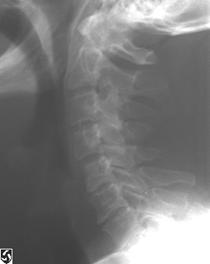

TRAUMA CERVICALA

Incidenta laterala Incidenta

laterala Incidenta

antero-posterioara

Aspect normal Imagine

incompleta Aspect

normal

Incidenta occipitomentala (odontoida)

Aspect normal Incidenta

oblica

Aspect normal

Incidenta oblica Incidenta laterala Incidenta antero-posterioara

Aspect normal Aspect normal Aspect normal